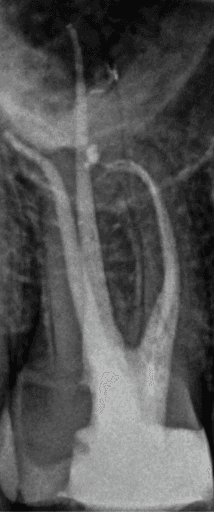

KREENA'S CASES